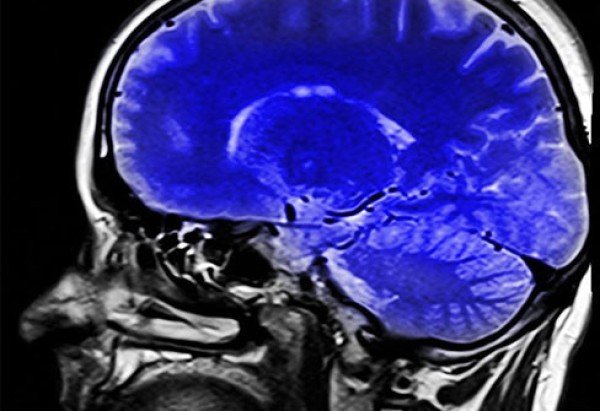

Pesquisadores da Bélgica identificaram uma nova população de células que atuam na proteção do cérebro humano. A descoberta, publicada na revista Nature Neuroscience, amplia a compreensão sobre como o órgão se defende contra substâncias nocivas e processos inflamatórios.

Considerado uma das estruturas mais complexas do corpo humano, o cérebro possui múltiplas barreiras de proteção que funcionam como filtros contra substâncias nocivas e patógenos. Uma das barreiras mais importantes, porém, menos conhecida é o plexo coroide, que envolve e protege o sistema nervoso central.

Para investigar essa questão, pesquisadores do Instituto Vlaams de Biotecnologia (VIB) e da Universidade de Ghent identificaram células chamadas de “células da barreira basal” que funcionam como um “portão inteligente”, formando uma vedação molecular capaz de bloquear até mesmo moléculas pequenas. Elas regulam o que pode atravessar entre o plexo coroide, o líquido cefalorraquidiano e o cérebro.

No entanto, em situações de inflamação sistêmica, essa barreira pode se tornar mais vulnerável, permitindo a entrada de substâncias nocivas no sistema nervoso.

Até então desconhecida, a chamada barreira basal abre uma nova via para entender como o sistema imunológico interage com o cérebro. A descoberta pode contribuir, no futuro, para o desenvolvimento de estratégias capazes de fortalecer essa proteção e auxiliar no tratamento de doenças neurológicas.